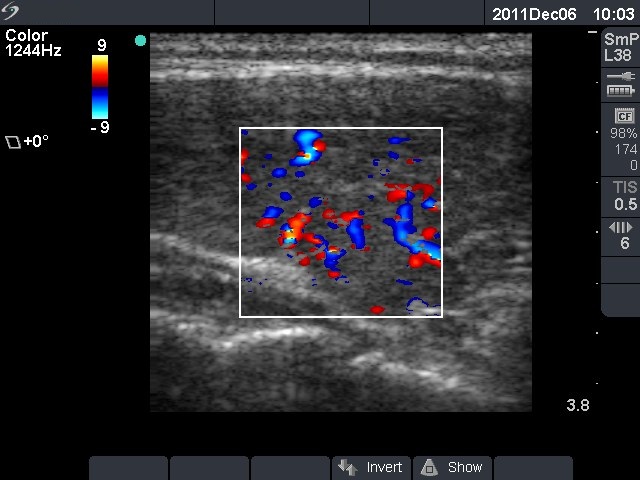

Ultrasonography: the thyroids were hypoechogenic without any nodule. The vascularization was increased.Cytology resulted in Hashimoto's thyroiditis.

Ultrasonography: the degree of hypoechogenicity and the previously increased vascularization have decreased, as did the size of the thyroid.

It is well-known that post partum state is practically the only one when even severe hypothyroidism may spontaneously normalize. The increased vascularization in a hyperthyroid state has little relevance. It may be observed in active hormone-producing disorders and in destructive process of autoimmune thyroiditis, as well.